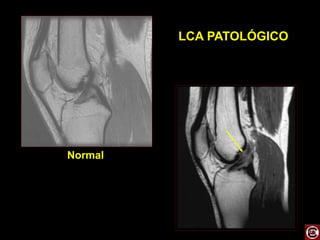

RM JOELHO

 Entorse

 Rompimento dos

ligamentos cruzados

anteriores e posteriores.

 Exame ouro pra estudo

do joelho.

LCA E LCP

LIGAMENTO CRUZADO

-

MENISCI PCL

ACL

MENISCI PATELLA TENDON

MEDIAL

LATERAL

QUADRICEPS TENDON

PATELLA

PATELLAR

TENDON

ANTERIOR CRUCIATE

LIGAMENT

POSTERIOR CRUCIATE

LIGAMENT Scan level

LCA PATOLÓGICO

Normal